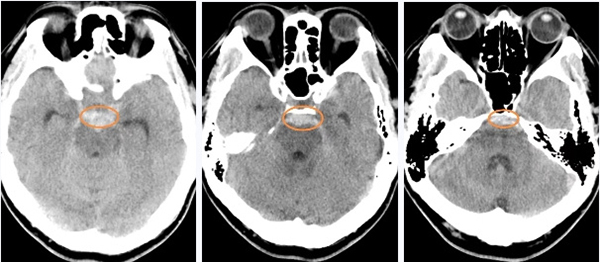

▲头颅CT检查提示蛛网膜下腔出血

主要位于脚间池,桥前池